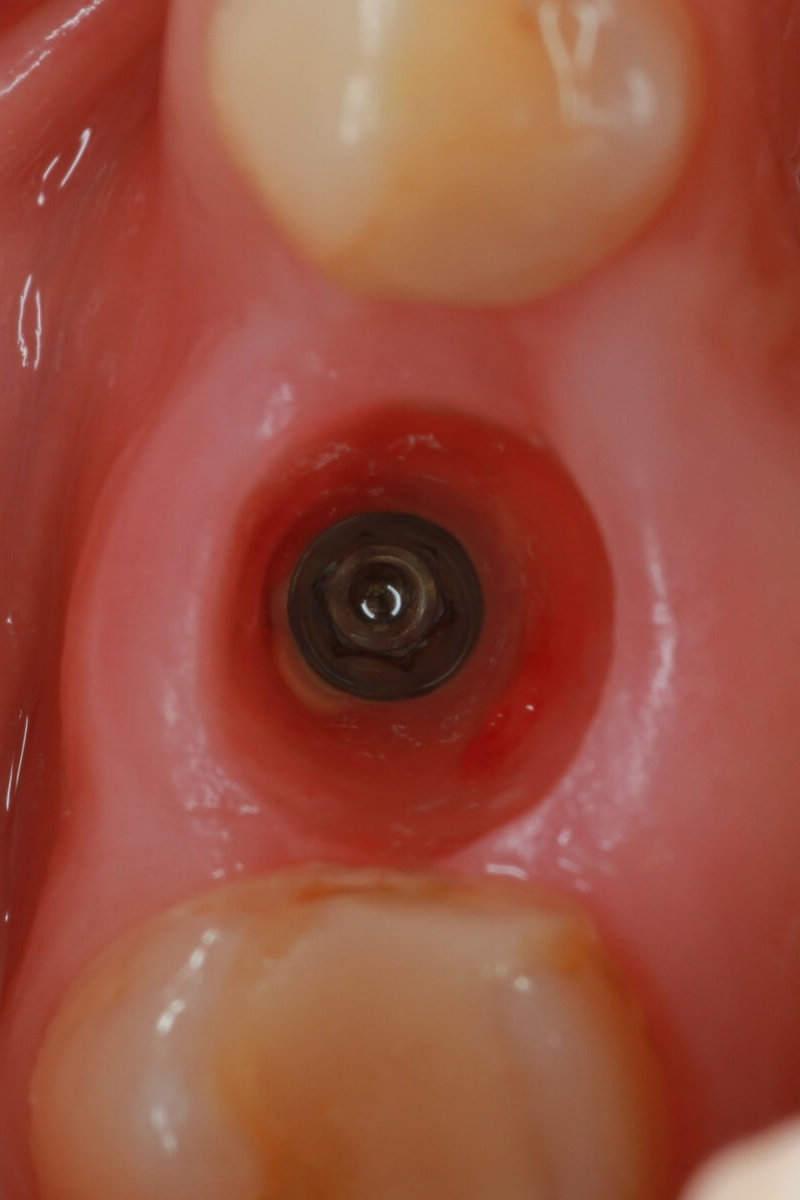

Installing the healing abutment

We install the gingiva former for 2-3 weeks in order to obtain an aesthetic gingival margin for subsequent prosthetics.